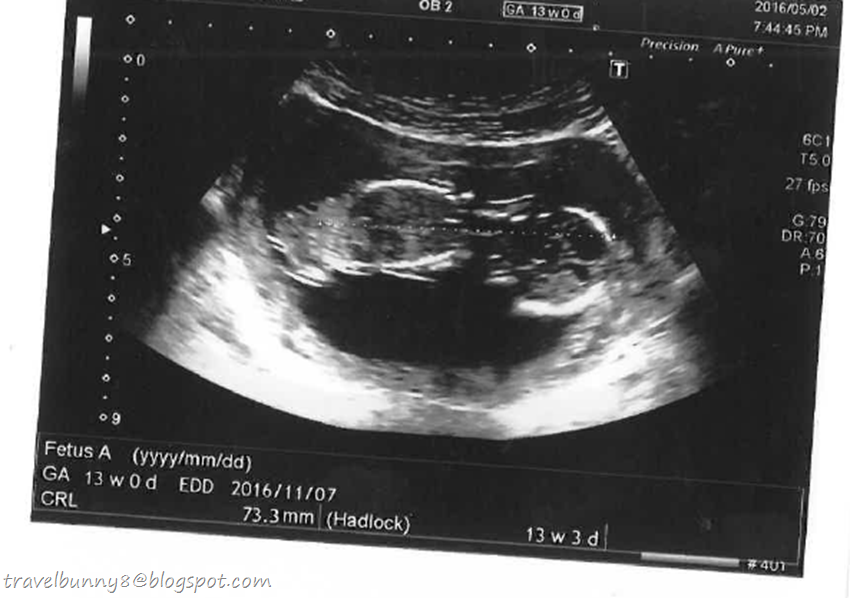

13 weeks pregnant. I was a little more anxious for the pregnancy this time as I decided to give birth in Qatar instead of going back to my home country, Malaysia. Everything was a bit different as compared to my first pregnancy. Here in Qatar hospital, the ultra sound, urine test, blood test and etc are done in separate departments, not by the same doctor and clinic like Malaysia. And every visit to the hospital was very time-consuming. In addition, the maternal expense is also doubled the price I paid for in Malaysia. Fortunately, my company insurance card covers half the cost.